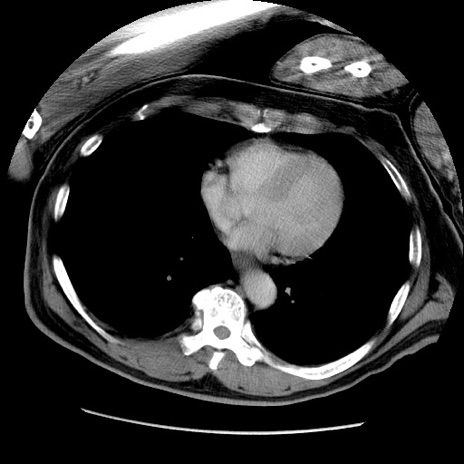

症例22(横断像)

【症例】50歳代男性

【主訴】腹痛

【現病歴】AVMからの被殻出血のため回復期リハ病棟入院中。 本日午後3時頃急に下腹部痛が出現した。

【既往歴】AVM、被殻出血、虫垂炎、高血圧

【身体所見】意識晴明、左半身不全麻痺、会話の理解は良好、36.5°C、腹部:膨隆、全体に板状硬、下腹部正中に圧痛点あり、反跳痛-、筋性防御不明、右下腹部にope scar

【データ】WBC 9400、CRP 0.06